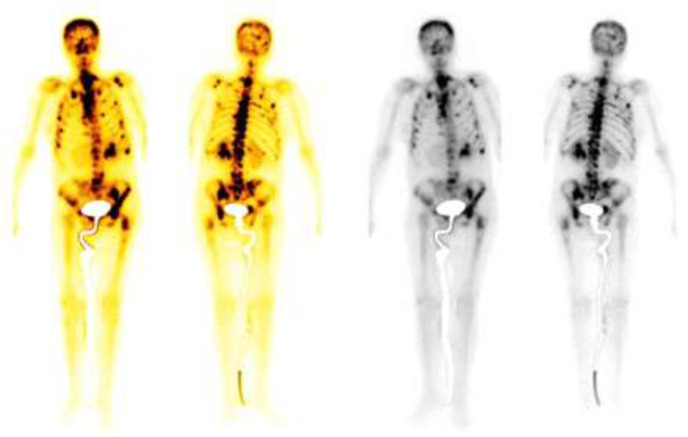

Case presentation: A 51-year-old woman presented with severe headache, vomiting, dizziness, blurred vision, tinnitus, bradyphrenia, reduced verbal fluency, sixth cranial nerve paresis, and non-reactive anisocoric pupils. Pleocytosis was found, with positive cytology for metastatic adenocarcinoma in cerebrospinal fluid, and a solid gastric mass defined as poorly differentiated adenocarcinoma. Due to her condition, the patient did not receive oncological management, evolving unfavorably and passing away twenty days later. Leptomeningeal carcinomatosis should be considered in patients with advanced cancer and meningeal symptoms. It is more predominant in women, with an average age of 53.84 years. Clinical presentation of leptomeningeal carcinomatosis varies, and diagnosis involves neuroimaging and cerebrospinal fluid cytology. Prognosis is unfavorable, often leading to fatality. Treatment protocols lack standardization, and personalized approaches, including targeted and systemic therapies, are explored for improved outcomes. The exceptional aspect of our case lies in the unique diagnosis of an abdominal tumor following the manifestation of neurological symptoms.

Abstract Image